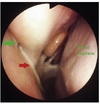

FIGURE 13 B, The corresponding right Plica vocalis at 30-50 days postsurgery on endoscopy. The Plica vocalis abscess clearly seen as a yellowish-greenish

mass covered in mucoid material (white arrow). Right to the left of the image